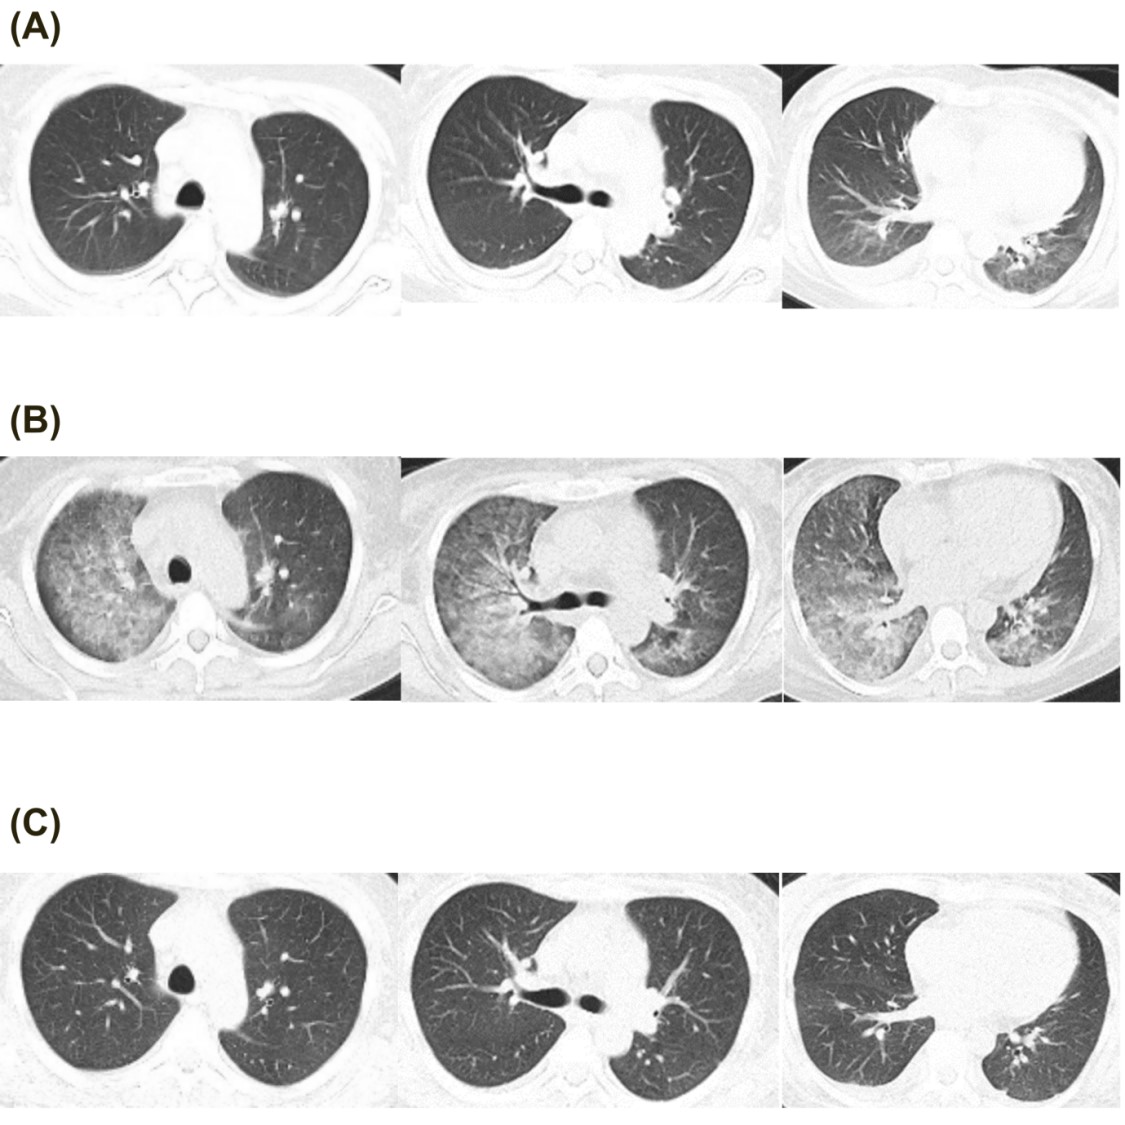

Laboratory tests showed leukopenia (WBC 2.09×10?/L), anemia (Hb 57 g/L), thrombocytopenia (PLT 21×10?/L), and nephrotic-range proteinuria (urinary protein ?3.0 g/L, RBC 277.5/µL, abnormal RBC percentage 60%, 24-hour urinary protein 2.50 g/1500 mL). Blood chemistry revealed hypoalbuminemia (Alb 14 g/L), normal liver enzymes and renal function. Complement levels were significantly reduced (C3 0.168 g/L, C4 0.007 g/L), with elevated anti-dsDNA IgG (1207.7 IU/mL) and positive direct Coombs' test. Infectious workup, including blood cultures, plasma CMV and EBV-DNA, and peripheral monocyte T-SPOT.TB, were negative. Chest CT (Fig. 1A) showed minor patchy infiltrates in the lower lungs, while abdominal ultrasound revealed gallbladder wall thickening with normal intestinal findings.

The SLE Disease Activity Index (SLEDAI) was 16, indicating severe disease activity. Methylprednisolone (MP) 500 mg daily for three days was initiated, followed by MP 80 mg daily for five days. By day 3, fever and digestive symptoms resolved, appetite returned, and bowel movements normalized. The hematologic abnormalities, and complement levels improved. However, on day 5, she redeveloped fever (Tmax 38.5°C), and by week 1, she developed hypoxemia, orthopnea, and hemoptysis (fresh bloody sputum). Examination revealed RR 30 bpm, SpO? 79% (RA) and bilateral lower lung crackles. BNP was elevated at 2190 ng/mL, and chest CT on day 7 (Fig. 1B) showed new diffuse peri-bronchovascular infiltrates. Left heart failure was suspected, and diuretics were administered. Meanwhile due to relapsed fever, empirical vancomycin and ceftazidime were initiated and MP was gradually adjusted to 40 mg once daily. There was no clinical evidence of skin and soft tissue infection, and both abdominal symptoms, urine bacteria culture and physical examination were normal. However, both blood and sputum from lower respiratory tract cultures identified MSSA via MALDI-TOF, leading to targeted therapy with amoxicillin-clavulanate for two weeks of whole antibiotic therapy. One week later, dyspnea resolved, hemoptysis ceased, SpO? normalized (97% RA), BNP decreased to 416 ng/ml and the infiltrates on chest CT disappeared (on day 14, Fig. 1C). Due to dynamic changes in imaging within a short timeframe, and diffuse bilateral ground-glass opacity, this strongly supports pulmonary edema over MSSA pneumonia itself, nor was it pulmonary involvement due to lupus activity.

Figure 1: Chest CT images. (A). CT at admission. (B). diffused glass ground opacity on CT after one week of admission. (C). infiltration disappear on CT after two week’s admission.